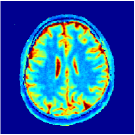

VI-E In-vivo experiments

Two sets of experiments were conducted here: first, we used the 2D and 3D acquisition sequences for scanning a healthy volunteer’s brain (real-world acquisitions). Figures 6 and 7 display the parametric maps reconstructed from 2D spiral and radial readouts. We computed the T1, T2 and proton density (PD) maps using baseline reconstruction algorithms ZF, VS, LR, FLOR, AIR-MRF and our proposed LRTV. While baselines use DM either for quantitative inference or also during reconstruction (i.e. AIR-MRF), we further compare the DM-free LRTV’s performance when cascaded to DM, KM and MRFResnet for quantitative inference. For the 3D spiral acquisitions we compared LRTV and its closest competitor VS in Figure 8. Outcomes from other tested algorithm are displayed in the supplementary materials (Figure S5). Since FLOR does not use dimensionality-reduction, our system ran out of memory during 3D reconstruction; hence results are not reported in this case.